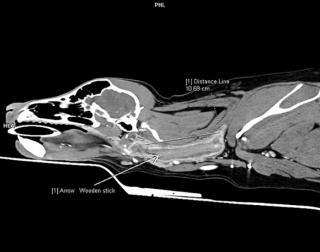

Malheureusement, l’état de Poppy ne s’est pas amélioré, car elle ne s’alimentait presque pas. Très inquiète, Amanda a alors emmené sa boule de poils dans une autre clinique, au Willows Veterinary Center and Referral Service. C’est la vétérinaire Erika Villedieu qui a alors pris Poppy en charge. Après lui avoir fait passer un scanner, elle a constaté qu’un morceau de bâton d’environ 10 centimètres était coincé dans la gorge du canidé. « Au début, nous avons été stupéfaits que Poppy se soit promenée avec ce bâton toujours à l'intérieur sans que personne ne s'en soit rendu compte », a raconté sa maîtresse.

© Willows Veterinary Center and Referral Service / Facebook